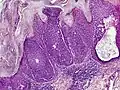

Dermoscopy and histopathology of eccrine poroma: (A) Clinical presentation of a nonpigmented eccrine poroma sensu stricto as a pink nodule located on the foot (B,C) Dermoscopy shows milky red areas (light blue arrow), milky red globules (dark blue triangle), and dotted vessels (black arrow) (original magnifications ×20 and ×40, respectively). (D,E) Histopathologically, the neoplasm consists of poroid and cuticular cells and tubular structures that are continuous with the epidermis (H&E stain, original magnifications ×10 and ×40, respectively).[19]

Microscopic histopathological examinations of the tumor tissues of all poroma variants stained with hematoxylin and eosin dyes reveal: a) basophilic "poroid cells" (i.e. small, cuboid-shaped cells with oval nuclei which resemble cells in the peripheral layer of the distal portion of eccrine sweat gland ducts[20]) that may form cords and broad columns extending downward from the epidermis; b) larger cuticular cells (i.e. squamous epithelial-like eosinophilic cells that resemble the luminal cells lining eccrine sweat gland ducts[20]); and in some cases c) clear cells (i.e. cells with small nuclei surrounded by pale cytoplasm).[3] Poroma tumor tissues may appear highly vascularized and/or have areas of necrosis, i.e. dead or dying cells. Hidroacanthoma simplex variants are mainly composed of poroid cells, few cuticular cells, and no clear cells and are confined to the epidermis; dermal ductal variants are mostly confined to the superficial dermis and are composed of small solid and cystic nodular aggregates of poroid, cuticular, and clear cells; poroid hidradenoma variants have large aggregates of solid and cystic components and extend deeper into the dermis or even subcutis; and eccrine poroma variants are composed of all three cell types but are primarily located in the epidermis and superficial dermis. Poromas may have 2 or more of these variants in the same tumor tissue and the variants typically have histopathology findings that are not clearly distinguishable from each other.[3]